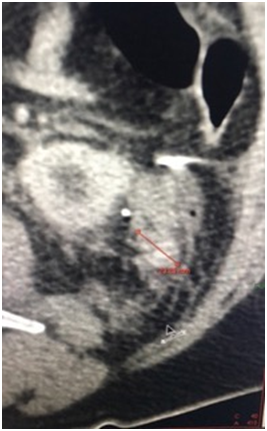

A 72 years old man was diagnosed with a small left renal mass incidentally during an ultrasonography for to an aortic abdominal aneurysm. A computer tomography (CT) scan confirm an exophytic 3cm left renal mass; therefore, an unclamped-laparoscopic partial nephrectomy was performed without difficulty. The tumor was placed inside of a plastic self-performed thermofused retrieval bag (Figure 1) and extracted trough a 12mm laparoscopic port. Finally, a drain was also placed close to the renorrhaphy. The patient was taken to the hospital room and in that moment, we realized that the bag was broken and the tumor was not inside. With the patient and family consent, a CT scan was performed showing a small mass next to the renorrhaphy (Figure 2); therefore, we decided to underwent an exploratory laparoscopy using the same port and patient position. Once laparoscopic camera was introduced, the tumor was found over the sigmoid colon slightly adhered (Figure 3) and extracted inside of a surgical glove. The hospital stay was 3 days with no perioperatory complications and the final histopathological finding was a 2cm cromophobo renal cell carcinoma with negative surgical margins.

Figure 1 Left: Plastic self-performed retrieval bag with the tumor inside. Right: broken bag at the time of tumor extraction.

Figure 2 Computer Tomography show the small renal mass close to the renorraphy.